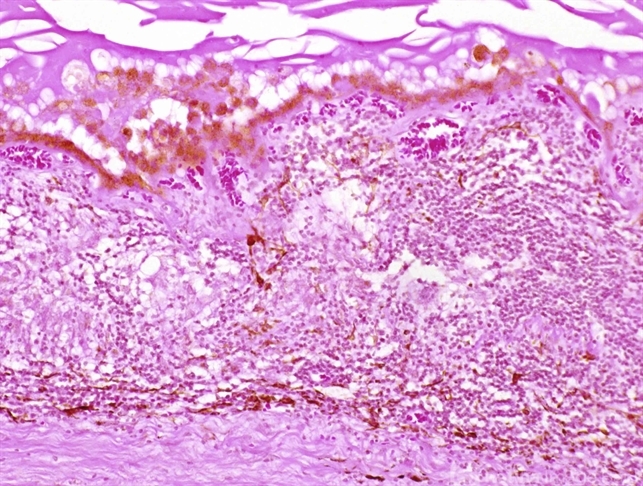

- An 45-year-old Asian descendant woman with poliosis and periocular vitiligo. Histopathology shows thickening of the choroid and chronic granulomatous choroiditis involving the choriocapillaris, typical of VKH.